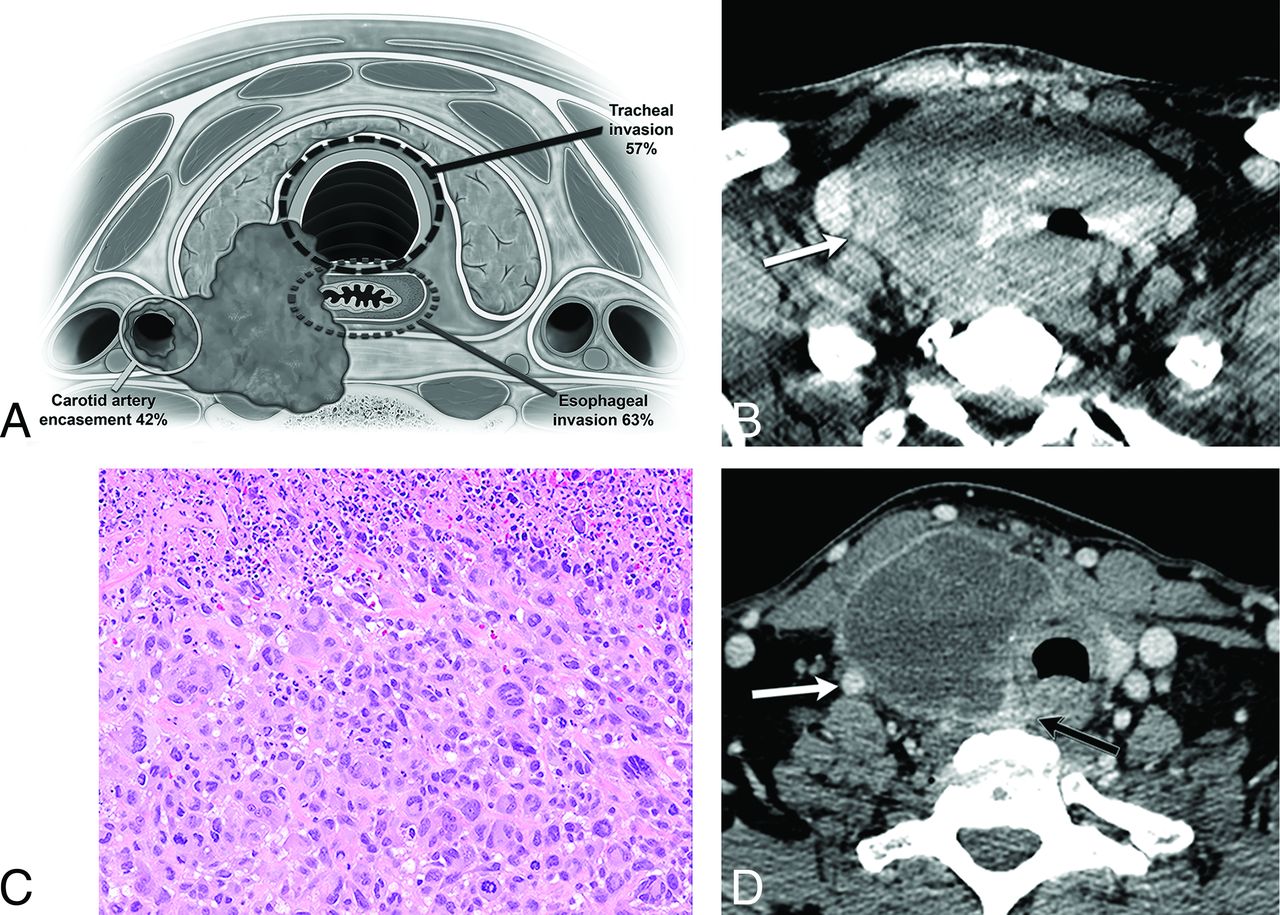

A 60-year-old man with enlarging right neck mass and hoarseness for 2 months with core biopsy demonstrating ATC, stage IVC. A, Graphic demonstrating the critical areas of evaluation to characterize the local invasiveness of an aggressive thyroid mass. B, Solid, heterogeneously enhancing right lobe tumor invades the trachea and esophagus, with leftward displacement of the midline structures, and encasement of the right ICA (arrow). C, Histologic features show enlarged, pleomorphic giant cells with hyperchromatic nuclei growing in sheets consistent with ATC. Necrosis with inflammation is common in these tumors as seen in the upper portion of this picture (hematoxylin-eosin tissue section at 200× magnification). D, After systemic therapy, the tumor mass has significantly decreased in size, with increased central necrosis, and improved overall local invasiveness. The right ICA is no longer encased (white arrow), and the tumor is now separable from the esophagus (black arrow).

Figure 3 shows the frequency of direct organ invasion and vascular involvement by ATC. The organ with the highest propensity for invasion was the esophagus (63%), followed by the trachea (57%) and the larynx (29%). Vascular involvement by the primary tumor was also commonly present, with carotid artery encasement in 42% of cases and internal jugular vein involvement in 43%. Direct intrathoracic extension of ATC was present in almost half the cases (24/57).

Anaplastic thyroid carcinoma propensity for organ invasion and vascular involvement.

Although ATC carries a dismal prognosis, improved survival can be achieved in select cases with a gross total resection in combination with chemotherapy/targeted therapy and radiation therapy. Therefore, precise tumor localization is imperative in determining and assessing treatment options. The primary factors that limit the possibility of meaningful surgery for a patient with ATC are carotid artery encasement (42% in our study), significant laryngeal and tracheal (57% and 29% in our study) or esophageal involvement (63% in our study), significant mediastinal extension, or significant regional or distant metastases. Although laryngotracheal and esophageal resections may be considered for less biologically aggressive tumors, these more complex surgeries and reconstructions are rarely attempted for patients with ATC because of the morbidity of the surgery in the setting of an overall very poor prognosis. Carotid encasement, which was present in 42% of our cases, would be considered inoperable. Similarly, reporting vascular involvement is also critical for the oncologist to counsel patients because this radiographic finding indicates the potential for local hemorrhage and death. Figure 4 demonstrates the typical imaging appearance of ATC at presentation in a patient who was initially deemed inoperable. After positive response to chemoradiation therapy, the carotid encasement and deep organ invasion were significantly improved. In a retrospective review of 121 patients with ATC, age <60 years, tumor size <7 cm, and less extensive disease at presentation were independently associated with decreased disease-related mortality.18 Increased survival is associated with surgical resection when feasible, younger age, smaller tumor size, higher dose of radiation therapy, absence of distant metastases at presentation, coexistence of papillary thyroid cancer, and management by using multimodal therapy.5,19 A retrospective review by Mohebati et al9 showed a 1-year survival of 54% with gross total resection of the primary tumor versus 28% with gross residual and 8% with no surgery.